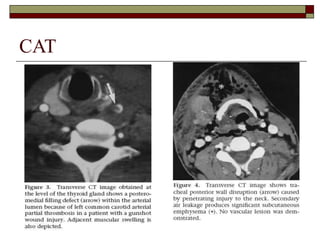

 CAT :

 En trauma penetrante: diagnóstico de lesiones

del confluyente laringotraqueal, como

complemento de la laringoscopía y

broncoscopía

 En trauma cerrado: evaluación de la laringe,

fracturas o lesiones complejas de la columna

vertebral o médula espinal

Multidetector CT ofthe neck reveals free air adjacent to the esophagus secondary to a traumatic perforation (arrows). CAT